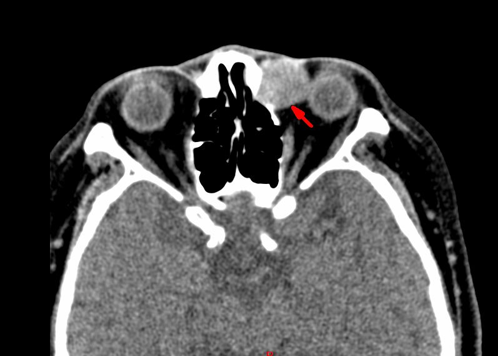

讲座|左泪囊肿瘤一例病例分享

DEK-AFF2 癌是鼻腔鼻窦非角化性鳞状细胞癌的罕见亚型,2022 年 WHO 头颈部肿瘤分类纳入其中。好发于男性(男女比例 3:2),年龄 18~79 岁(中位 58 岁),多见于鼻咽、鼻腔和鼻窦等部位,泪囊发病罕见